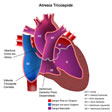

Atresia de la valvula tricuspide En esta malformación hay atresia de la válvula tricúspide, comunicación interauricular y, con frecuencia, hipoplasia del ventrículo derecho y de la arteria pulmonar. En clínica suele predominar una cianosis intensa, a consecuencia de la mezcla obligada de sangre de la circulación general y pulmonar en el ventrículo izquierdo. El electrocardiograma muestra ...

Atresia de la valvula tricuspide En esta malformación hay atresia de la válvula tricúspide, comunicación interauricular y, con frecuencia, hipoplasia del ventrículo derecho y de la arteria pulmonar. En clínica suele predominar una cianosis intensa, a consecuencia de la mezcla obligada de sangre de la circulación general y pulmonar en el ventrículo izquierdo. El electrocardiograma muestra ... -